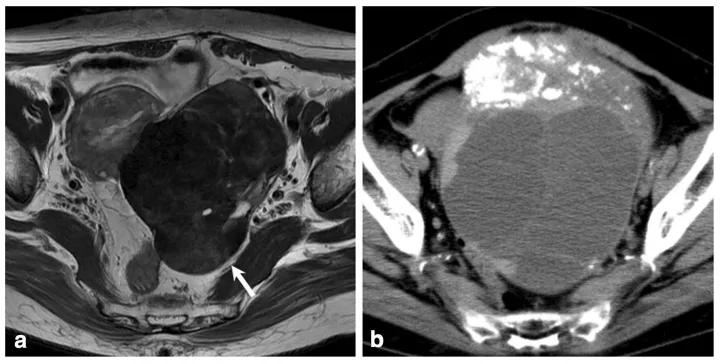

女,34 岁,胃癌双侧卵巢转移瘤。T2WI 显示双侧卵巢实性肿瘤,T2WI 呈高低混杂信号(图 a),DWI 呈高信号(图 b)。

女,12 岁,卵巢 Burkitt 淋巴瘤。双侧卵巢肿物,T2WI 信号稍高(图 a),DWI 呈高信号(图 b),增强扫描明显强化(图 c),箭头显示肿物边缘多发囊性结节,为卵泡保留征。